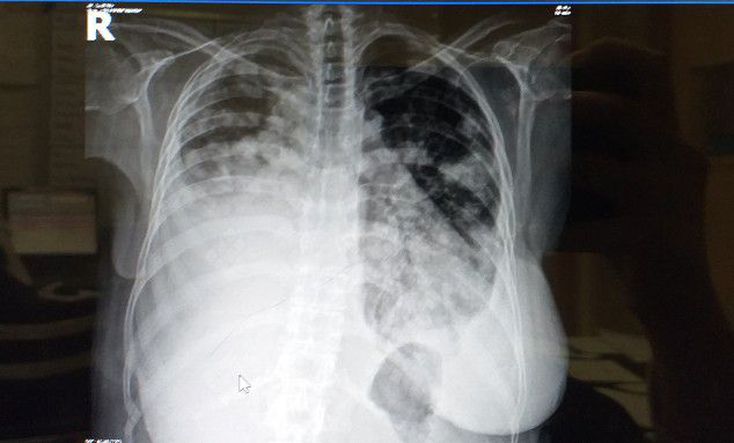

68 year old woman with dyspnea.

What is your diagnosis?

Rt sided pleural effusion With patchy pneumonia

Good DDX, pleural effusion due to lung cancer

Lung metastasis from breast cancer🤔

Good, its plural effusion due to lung cancer